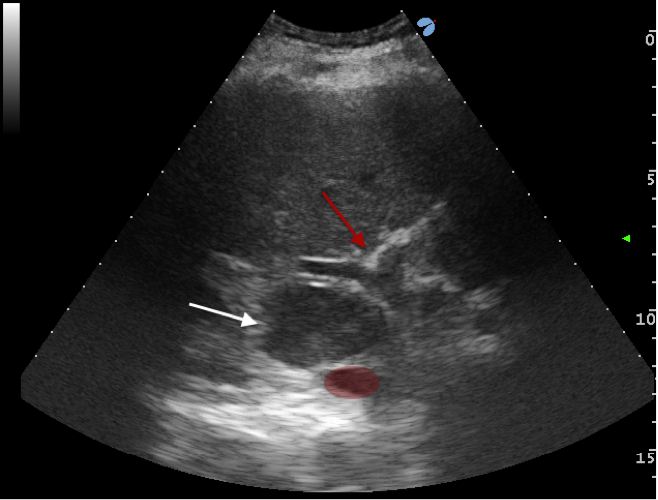

Un paziente con lesione epatica (freccia bianca in Figura), parzialmente esofitica, posizionata tra un ramo della vena porta e la vena cava, è stato sottoposto a Termoablazione con EchoLaser, utilizzando 4 fibre due posizionate nella parte superiore della vena porta e due nella parte inferiore. La lesione, particolarmente difficile da trattare per gli elementi vascolari che la circondano, è stata ablata completamente senza alterazione delle strutture vascolari circostanti.

Immagine ecografica prima del trattamento